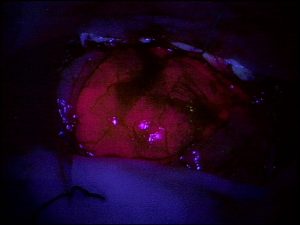

Gehirnmetastasen: Erleichtert Fluoreszenz-Markierung die operative Entfernung von Tumoren?19. Mai 2020 Metastase in situ: Rot=Fluoreszens. (Foto: © Franz Marhold) Mediziner der Karl Landsteiner Privatuniversität für Gesundheitswissenschaften Krems (Österreich) haben Ergebnisse der weltweit größten Studie zur Bewertung von 5-Aminolävulinsäure vorgelegt. Zwei Drittel der Gehirnmetastasen zeigen nach Gabe von 5-Aminolävulinsäure eine Fluoreszenz, die für Operateure potenziell hilfreich bei der Identifizierung sein könnte. Allerdings ist diese Fluoreszenz oft sehr ungleichmäßig verteilt oder schwach – was den Nutzen in der Praxis limitiert. Das ist das Ergebnis einer großen Studie der Karl Landsteiner Privatuniversität für Gesundheitswissenschaften Krems (KL Krems) unter der Leitung der Medizinischen Universität Wien. Mit mehr als 150 Patienten ist die im „Journal of Neurosurgery“ veröffentlichte Studie die weltweit bisher umfangreichste ihrer Art und liefert aussagekräftige Ergebnisse. Diese bilden den Autoren zufolge eine wertvolle Grundlage für die Weiterentwicklung dieser potenziell hilfreichen Technologie. Gehirnmetastasen sind die häufigsten Tumore im Gehirn und treten bei 20 bis 40 Prozent aller systemischen Krebserkrankungen auf. Oftmals werden sie durch chirurgische Eingriffe entfernt, was eine wichtige Behandlungsoption neben Strahlentherapie, Gamma Knife oder Chemotherapie darstellt. Sie gelten dabei als zumeist gut operativ entfernbar, da sich Metastasen vom umgebenden Gewebe häufig gut abgrenzen lassen. Doch kürzlich wurde festgestellt, dass nach circa 20 Prozent aller chirurgischen Entfernungen kleine Resttumore verbleiben. Eine Möglichkeit, Chirurgen auch diese schwer entdeckbaren Tumorteile bei der Operation erkennbar zu machen, könnte es sein, die Operation nach Gabe von 5-Aminolävulinsäure (5-ALA) durchzuführen. Diese Substanz erzeugt speziell in Tumorzellen eine leicht erkennbare Fluoreszenz und erlaubt es so, Tumorreste besser zu erkennen. Für Primärtumore im Gehirn ist diese Technik bereits etabliert, doch für Gehirnmetastasen wurde sie noch nicht ausreichend systematisch untersucht. Genau das hat nun ein Team der KL Krems und der MedUni Wien in der weltweit größten Studie ihrer Art getan– und ist zu ernüchternden Ergebnissen gekommen. Metastase in situ. (Foto: © Franz Marhold) Metastasen markieren „In zwei Drittel aller mit 5-ALA vorbehandelten Metastasen konnten wir eine sichtbare Fluoreszenz nachweisen“, erläutert der Erstautor der Arbeit, Dr. Franz Marhold (Klinische Abteilung für Neurochirurgie des Universitätsklinikum St. Pölten der KL Krems), „doch war diese Fluoreszenz wenig intensiv oder oftmals ungleichmäßig verteilt, was den Nutzen in der Praxis derzeit leider beschränkt.“ Tatsächlich untersuchte das Team insgesamt 157 Gehirnmetastasen bei 154 Patienten. Bei 104 Gehirnmetastasen wurde eine 5-ALA Fluoreszenz nachgewiesen, bei 53 Tumoren nicht. Bei mehr als 80 Prozent der Metastasen war die Fluoreszenz jedoch so ungleichmäßig verteilt, dass diese Information für Chirurgen wenig hilfreich für die Tumorentfernung ist. Ein wesentliches Merkmal dieser umfassenden Studie war dabei jedoch, dass die untersuchten Fluoreszenzkriterien (Vorhandensein, Intensität, Verteilung) mit den verschiedenen Krebsarten des Primärtumors in Verbindung gebracht werden konnten. Dazu Prof. Georg Widhalm, Universitätsklinik für Neurochirurgie der MedUni Wien und Leiter der Studie: „Wir untersuchten vor allem Gehirnmetastasen von Lungen-, Brust-, Darm-, Haut- und Nierenkrebsbetroffenen. Die Auswertung der Fluoreszenzmarkierung zeigte, dass diese bei Metastasen von bestimmten Brustkrebstumoren am häufigsten und bei solchen von Hautkrebstumoren am seltensten zu erkennen war. Die unregelmäßige Verteilung und schwache Intensität der Fluoreszenz im Tumor hingegen war für alle Krebsarten ähnlich.“ Gute Grundlage Die Ursache für die oftmals schwache Fluoreszenz bei Gehirnmetastasen konnte im Rahmen der Studie nicht ermittelt werden, doch erlauben die gesammelten Daten und Tumorproben mögliche Ursachen zukünftig zu untersuchen. Gleiches gilt für die Ungleichmäßigkeit der Fluoreszenz innerhalb einzelner Metastasen. „Hier vermuten wir, dass es innerhalb des Tumors eine unterschiedliche Verteilung bestimmter Stoffwechselprodukte gibt, die mit 5-ALA reagieren und somit eine unterschiedliche Verteilung der Fluoreszenz bewirken“, meint Marhold. Auch dies soll in zukünftigen Arbeiten geklärt werden.